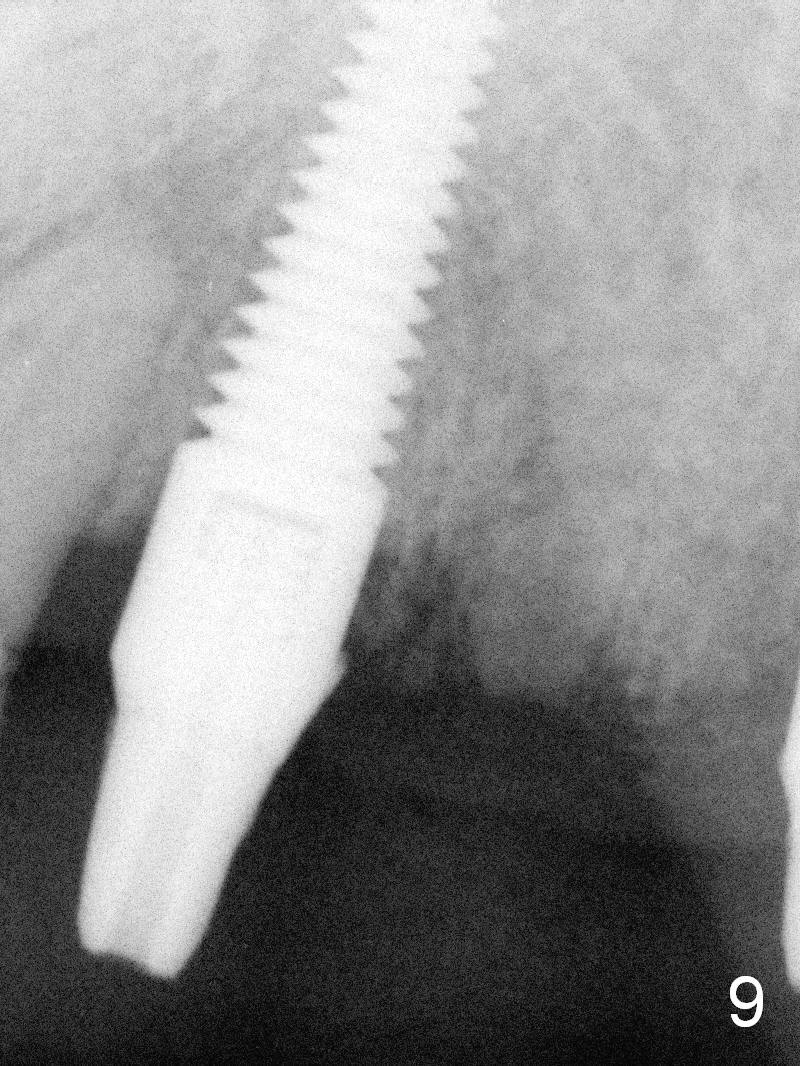

The patient returns for definitive restoration 3.5 months postop (Fig.9).  Osteointegration appears to have occurred at #11.